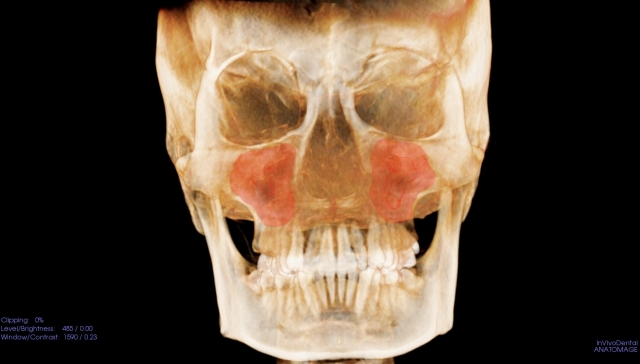

頬骨_痛い時_頬骨の高さの水平線

上のラインで、顔を輪切りにすると。

頬骨_痛い時_頬骨と上顎洞

CT像は、こうなります。

頬骨の裏には、

上顎洞という空洞(副鼻腔)があります。

頬骨が痛い事は、

上顎洞炎(副鼻腔炎)と、

関係が近いと言えます。